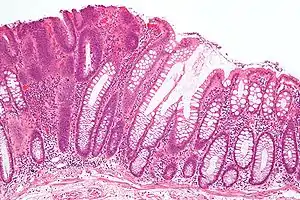

Micrograph of a tubular adenoma (left of image), a type of colonic polyp and a precursor of colorectal cancer. Normal colorectal mucosa is seen on the right of the image. H&E stain.

Adenoma is a benign tumor of glandular tissue, such as the mucosa of stomach, small intestine, and colon, in which tumor cells form glands or gland like structures. In hollow organs (digestive tract), the adenoma grows into the lumen - adenomatous polyp or polypoid adenoma. Adenomatous polyps may be classified based on morphology in order to identify lesions at increased risk of malignant transformation. For example, adenomatous polyps in the colon may be pedunculated (lobular head with a long slender stalk) or sessile (broad base).

The adenomatous proliferation is characterized by different degrees of cell dysplasia (atypia or loss of normal differentiation of epithelium) irregular cells with hyperchromatic nuclei, stratified or pseudostratified nuclei, nucleolus, decreased mucosecretion, and mitosis. The architecture may be tubular, villous, or tubulo-villous. Basement membrane and muscularis mucosae are intact.